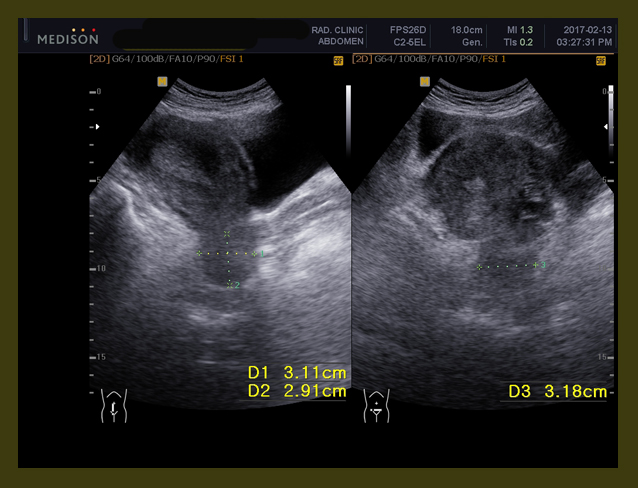

초기에 수술 전에 약 3.2×3.0cm 정도의 크기를 보였고 우측 유방절제 후에 소음인에게 잘 맞는 AC 요법을 4 차 2016년 9월부터 2017년 1월까지 시행하였다.

• 2016년 4월 14일  본원  한약조치 이후  5cm의 종양  3.9 cm로 줄어들음

• 2016년 9월 8일  2.3cm(2016/5/26) —-> 1.13cm(2016/9/8)

• 2016년 10월 13일 약 10mm  x 2mm의 종양의 괴사된 흔적 남아 보임

이후 방사선이 끝나고 내원하여 9월 달 보니 종양의 거의 괴사되어서 1.13×0.58cm의 크기가 남아 있었고 한달 뒤인 2016년 10월 13일에는 1.03×0.2cm 정도의 괴사된 흔적만 보였다.